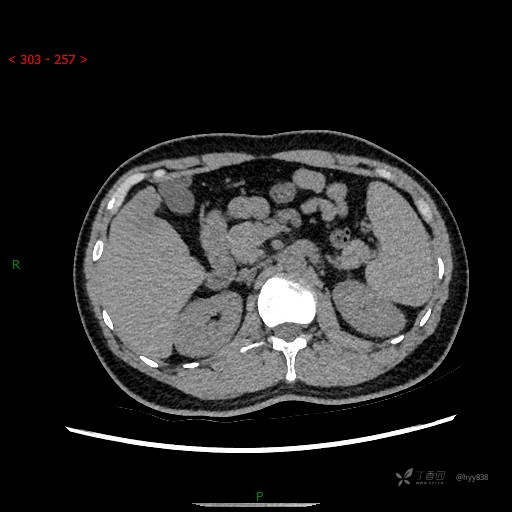

肝脏CT平扫

增强动脉期